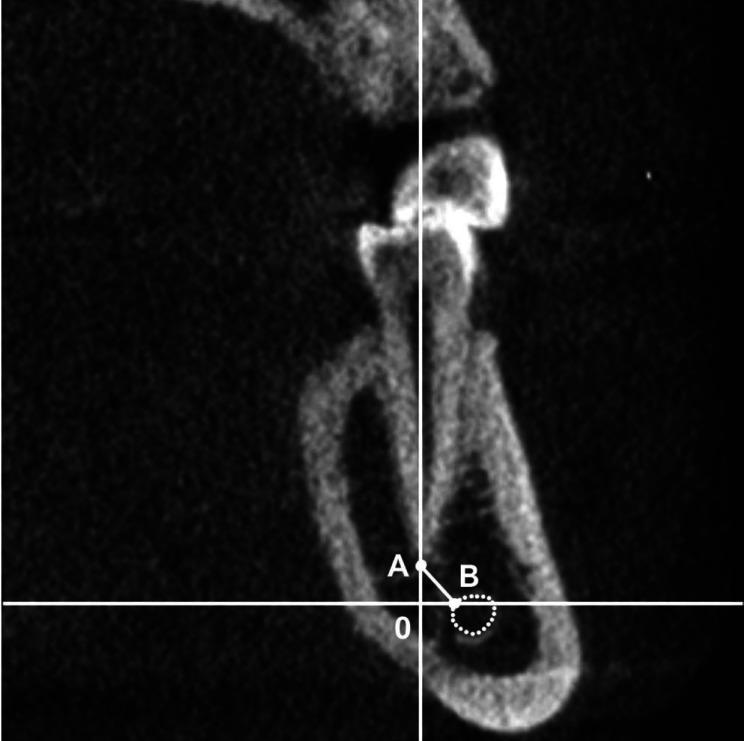

Images of 300 volumetric tomography scans of patients aged between 20 and 79 years old (167 women and 133 men) were analysed. The mean distances between 2,053 dental root apices and the internal border of the MC were obtained by measuring the horizontal and vertical distances on coronal CBCT images. The actual distance was then calculated mathematically with the Pythagorean formula. The statistical significance of differences between men and women was assessed using the Mann-Whitney test. Correlations with patient age were evaluated with the Spearman rank correlation coefficient.

分析了300例年龄在20至79岁之间患者(167名女性和133名男性)的容积断层扫描图像。通过测量冠状面CBCT图像上的水平和垂直距离,得出2053个牙根尖与下颌管内边界之间的平均距离。然后用勾股定理进行数学计算得出实际距离。采用Mann-Whitney检验评估男女之间差异的统计学意义。用Spearman等级相关系数评估与患者年龄的相关性。